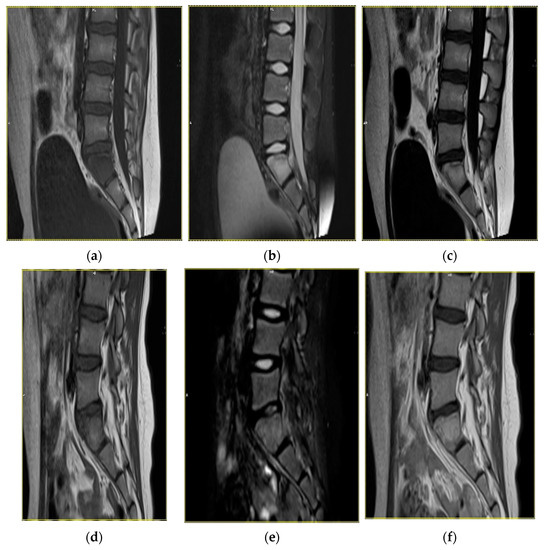

The duration of follow-up of the study patients varied between 3 months and 3 years. In 40% of the patients, both clinical symptoms and radiological abnormalities resolved completely, whereas another 50% of patients showed partial regression of clinical and radiological manifestations. In the remaining 10% of the patients, follow-up was too short to confirm progression/regression of the disease (Figure 2, Figure 3 and Figure 4).

Figure 2. Magnetic resonance images in a 10-year-old female patient with inflammatory lesions around the left sacroiliac joint. Status before treatment: T1-weighted sequence (a), T2-weighted sequence (b), T1-weighted sequence with contrast enhancement (c). Status after a 19-month follow-up, with partial regression of the inflammatory lesions: T1-weighted sequence (d), T2-weighted sequence (e), T1-weighted sequence with contrast enhancement (f).

All patients with a presumptive diagnosis of CRMO underwent MRI (Table 3). Most patients presented with multifocal hypodense areas on T1-weighted images, with the enhancement of signal on T-weighted and STIR sequences. Additionally, the areas involved with the inflammatory process showed an intensive contrast enhancement. Furthermore, MRI demonstrated swelling of adjacent soft tissues and bone marrow edema. The abnormalities described above, in particular bone lesions, were found in all patients diagnosed with CRMO. Typical MRI findings in the thoracic and lumbar spine included the decreased height of vertebral bodies and bone marrow edema.

MRI also remains the most accurate diagnostic option in patients with relapse. In 30% of patients included in this study, MRI demonstrated progression of primary foci as well as secondary foci, usually in the proximity of the primary foci or in the thoracic/lumbar spine. Clinically, such patients presented with pain of the involved anatomical area and/or impaired function of adjacent joints. Our study also confirmed the role of MRI as a gold diagnostic standard in patients with remission. In such patients, MRI showed a substantial decrease in the size of inflammatory foci within the bone, regression of bone marrow edema and resolution of lesions in adjacent soft tissues. Such radiological presentation correlated with partial or complete remission of clinical symptoms.